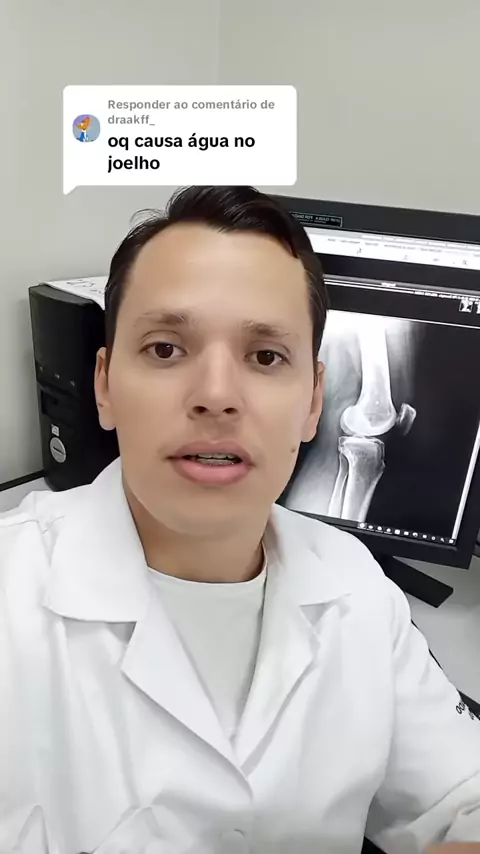

A responder a @aczin.editx sobre o porquê ocorre o acúmulo de "água" no joelho 🤙🏻

A responder a @draakff_ sobre água no joelho citei as principais causas, espero ter ajudado 🤙🏻